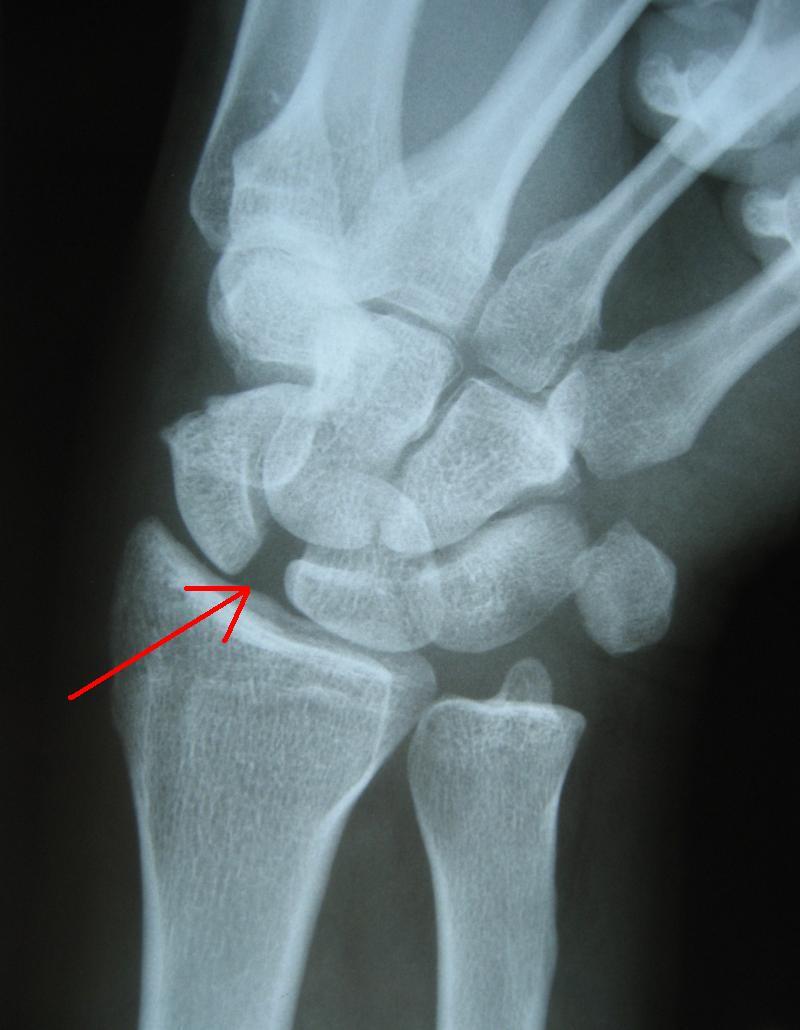

그래서 관절이 거의 탈구될 정도로 인대가 늘어난 게 아니라면, 염증이 발생할 정도로 손상된 게아니라면, 영상장비로는 그 이상을 파악하기 어렵다.

그러니 x-ray, mri만 찍고 정상이라고 해서 진짜 정상은 아니며, 반드시 인대나 근육의 기능이 정상적인지는 별도로 확인해야 할 것이다.